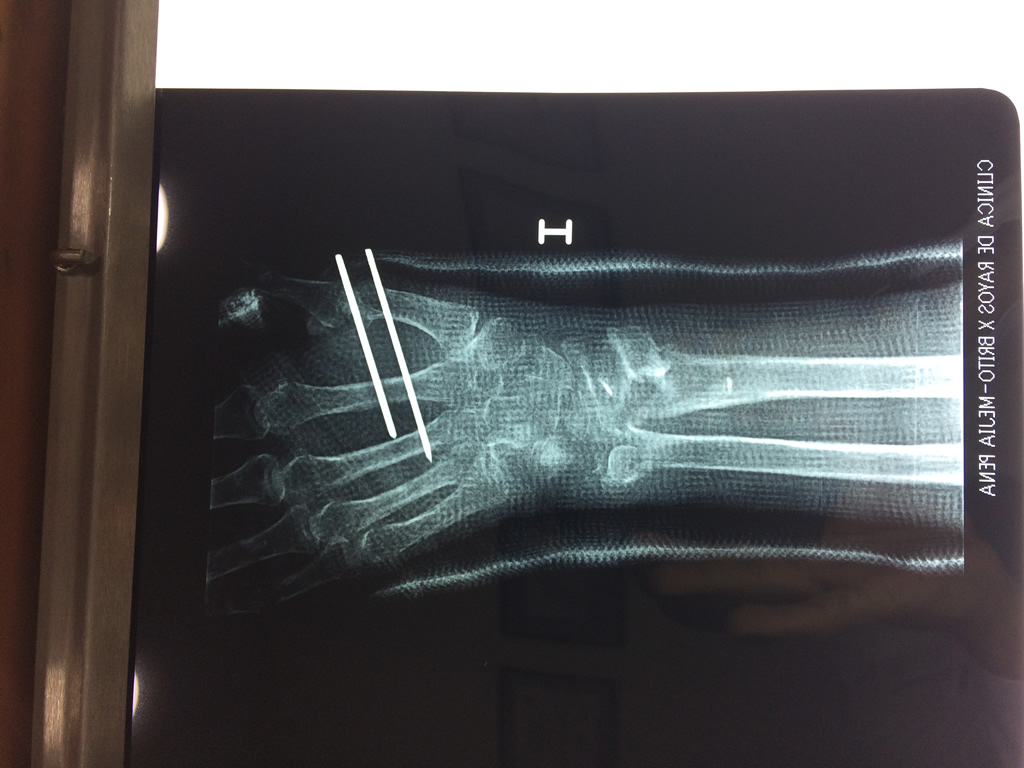

Cirugías de Calcaneo - Cirugías de Muñecas y Manos

Los procedimientos más comunes en cirugía de la mano son aquellos destinados a reparar traumatismos, incluyendo lesiones de tendones, nervios, vasos sanguíneos, y articulaciones; huesos fracturados; y quemaduras, cortes, y otros daños de la piel.